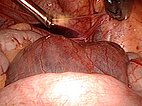

Laparoskopische Resektion von mehr als 90 % der Zysten. Hier Blick auf die von dorsal durch das Peritoneum sichtbaren, retroperitoneal gelegenen Zysten der LM.